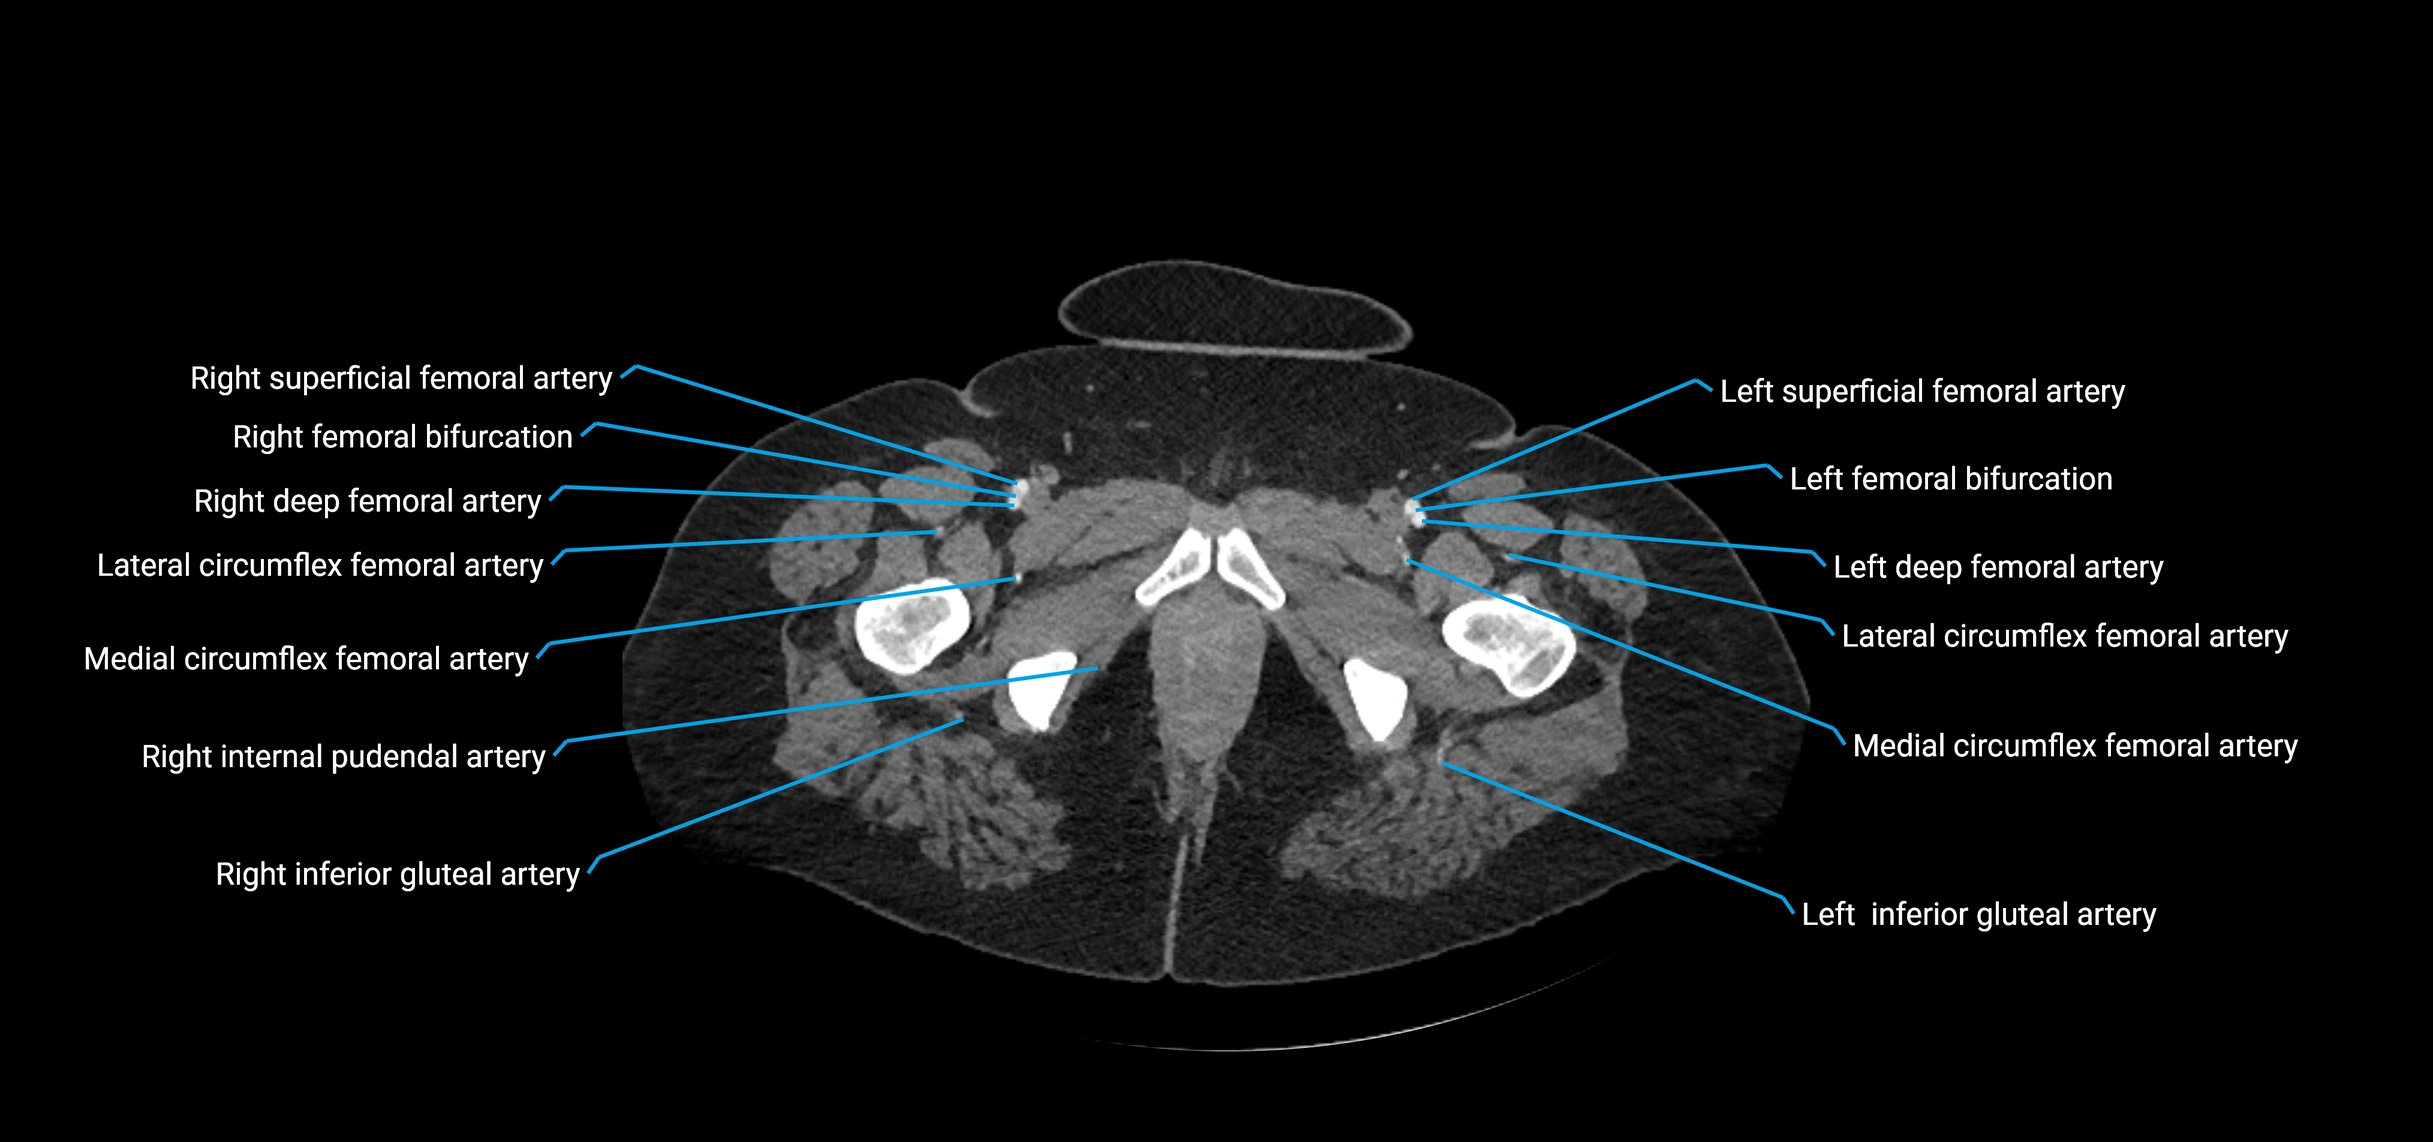

CT images

image

Contrast-enhanced CT (CTA):

• Gold standard for abdominal aortic imaging

• Provides excellent detail of lumen, wall, aneurysm, thrombus, and branch vessels

• Multiplanar and 3D reconstructions help in aneurysm measurement, stent graft planning, and dissection evaluation